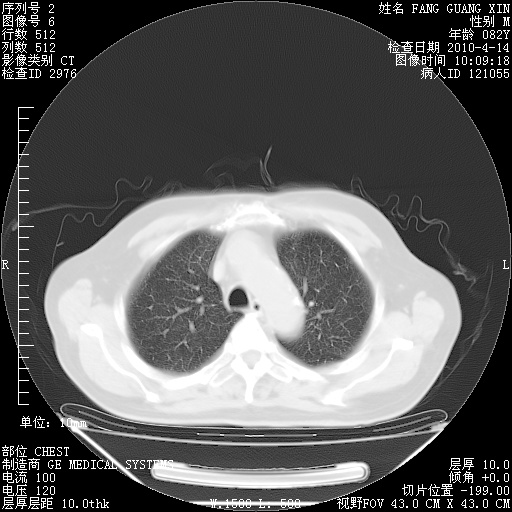

4月14日肺部CT